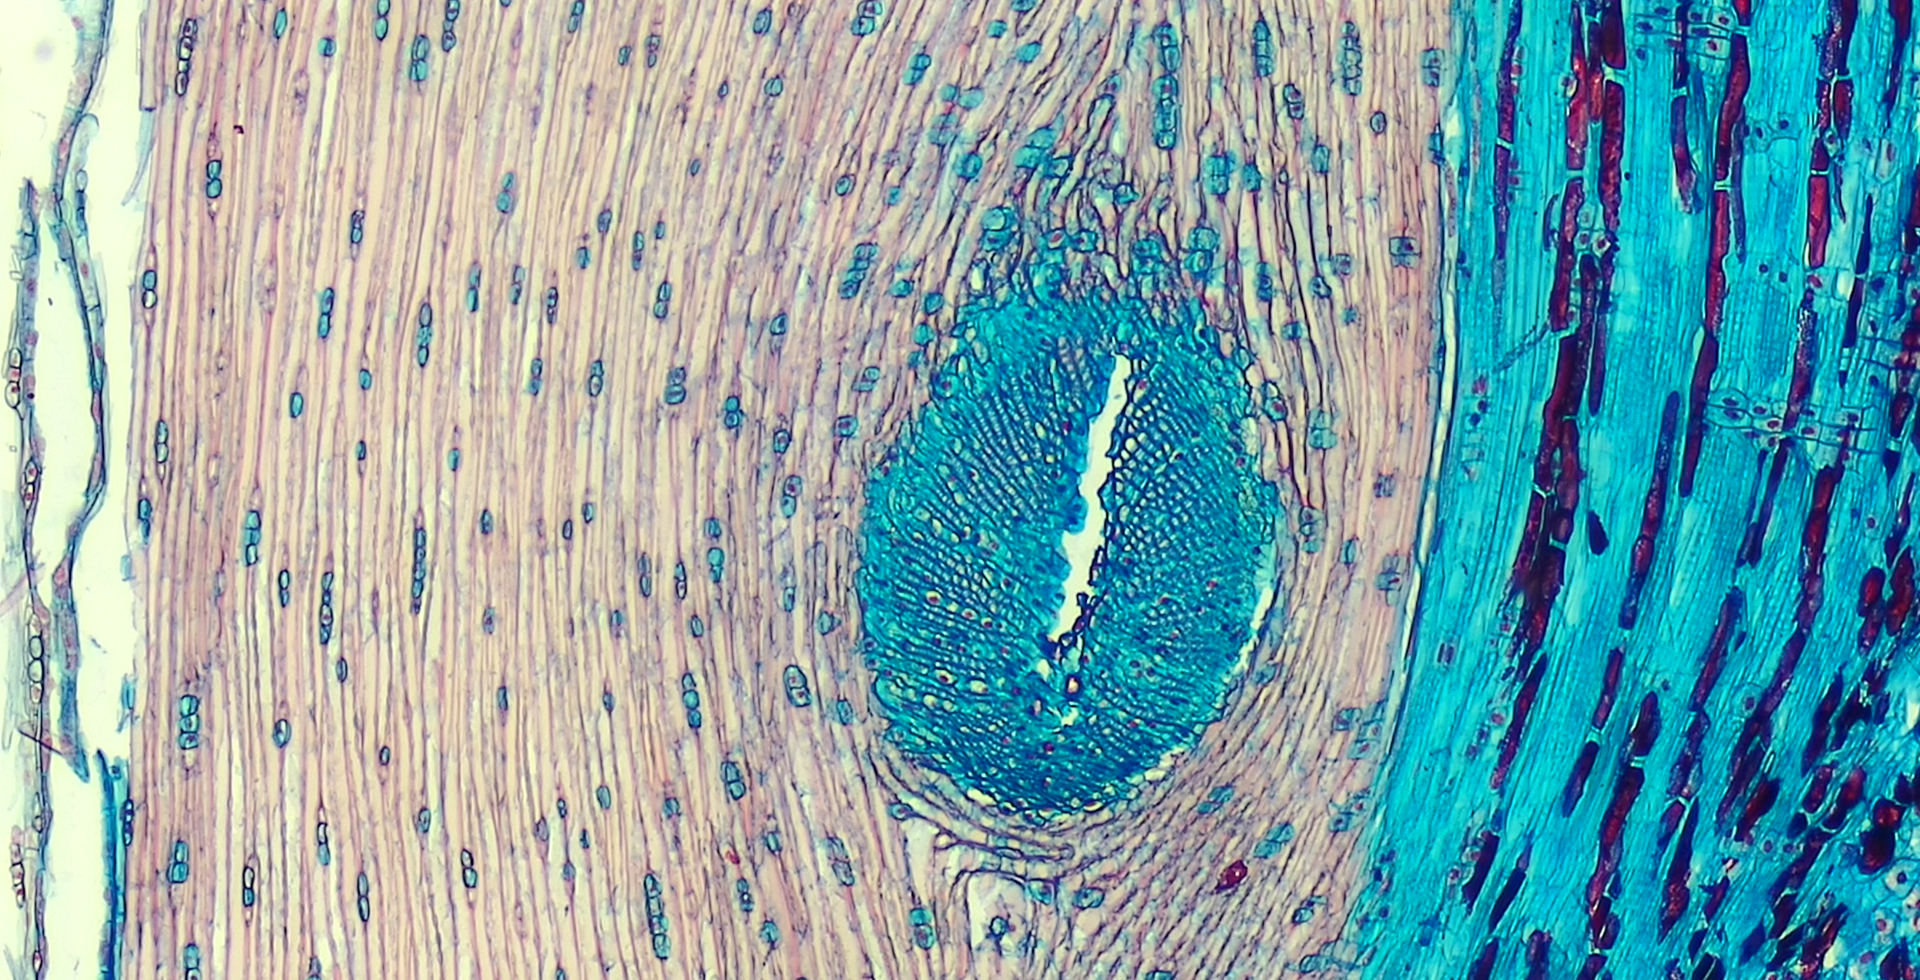

Color Tissue Section